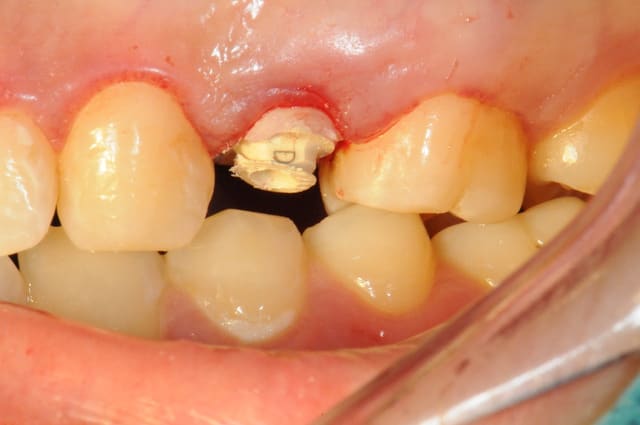

je rebondis sur ton titre" ne jamais faire de jolie provisoire", car ça me rappel une patiente.

25 ans, implanté en 2009

extraction-Summers-implantation- MCI sur une "jolie" provisoire avec du composite montée sur un pilier en pick...

(dernière photo contrôle à 15jours)

je l'ai rappelé il y a un an; pas de nouvelles, la provisoire doit lui convenir...

ps: c'est peu être le seule implant dont j'espère qu'il tombera. NA!

conclusion: ne jamais faire de jolie provisoire